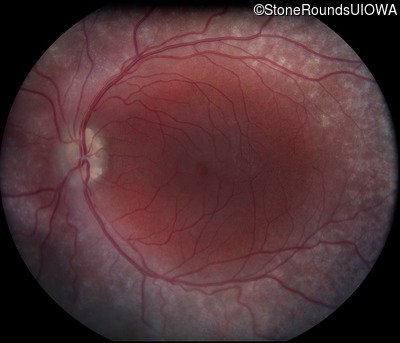

Fundus Photography - Right - 20/40 +2

Exemplar